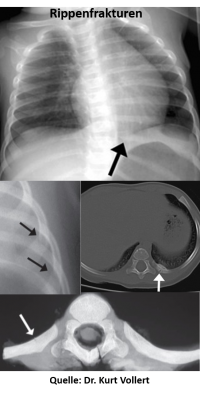

In einem speziellen Vortragsblock referiert Vollert als Vertreter der Augsburger Kinderradiologe auf dem Bayerischen Röntgenkongress über die typischen Anzeichen von Gewalt gegen Kinder. In der Mehrzahl der Fälle äußert der behandelnde Arzt den Verdacht auf Misshandlung, manchmal wird die Misshandlung jedoch erst im Rahmen einer bildgebenden Untersuchung zufällig entdeckt. „Der klassische Fall: Man macht eine Röntgenaufnahme der Lunge und stellt zum Beispiel ältere Rippenfrakturen fest. Das ist hochverdächtig“, erklärt Vollert.

Zu den typischen Verletzungen infolge von Misshandlung zählen Extremitätenfrakturen bei Säuglingen, die sich noch nicht eigenständig fortbewegen können und bei denen deshalb ein Unfall als Ursache unwahrscheinlich ist, oder Rippenfrakturen und Brüche der Extremitäten, sofern keine Krankheit bekannt ist, die Einfluss auf die Knochenstabilität hat. Rippenfrakturen oder Organverletzungen deuten häufig auf ein bewusstes Zusammendrücken des Brustkorbs hin.

Zu den typischen Verletzungen infolge von Misshandlung zählen Extremitätenfrakturen bei Säuglingen, die sich noch nicht eigenständig fortbewegen können und bei denen deshalb ein Unfall als Ursache unwahrscheinlich ist, oder Rippenfrakturen und Brüche der Extremitäten, sofern keine Krankheit bekannt ist, die Einfluss auf die Knochenstabilität hat. Rippenfrakturen oder Organverletzungen deuten häufig auf ein bewusstes Zusammendrücken des Brustkorbs hin.